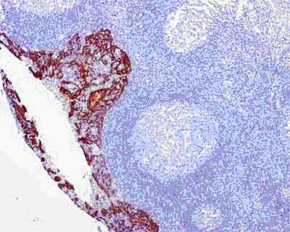

Immunohistochemistry (Formalin/PFA-fixed paraffin-embedded sections) - Anti-Cytokeratin 16/K16 antibody [EPR13504] - BSA and Azide free (AB240236)

Immunohistochemical analysis of paraffin-embedded Human tonsil tissue labeling Cytokeratin 16/K16 with ab181055 at 1/500 dilution followed by pre-diluted HRP-conjugated secondary antibody and counter-stained with Hematoxylin.

This data was developed using the same antibody clone in a different buffer formulation containing PBS, BSA, glycerol, and sodium azide (ab181055).

Perform heat mediated antigen retrieval with EDTA buffer pH 9 before commencing with IHC staining protocol.